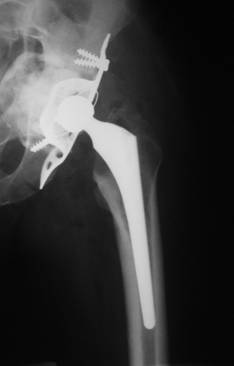

Artroplastiile s-au realizat in doua interventii operatorii la distanta de 6 luni, initial pe partea dreapta (fig. 2), unde s-a instalat initial decompensarea algica si apoi pe partea stanga (fig. 3), unde a fost necesara crearea unui nou fund al acetabulului cu ajutorul unui inel de ranforsare insurubat tip Brch-Schneider. Intre inel si acetabul s-a introdus o grefa osoasa cortico-spongioasa recoltata din creasta iliaca. Pe ambele parti, componenta femurala a fost de tip necimentat.

Fig. 3. Rezultat final la 1 an postoperator.